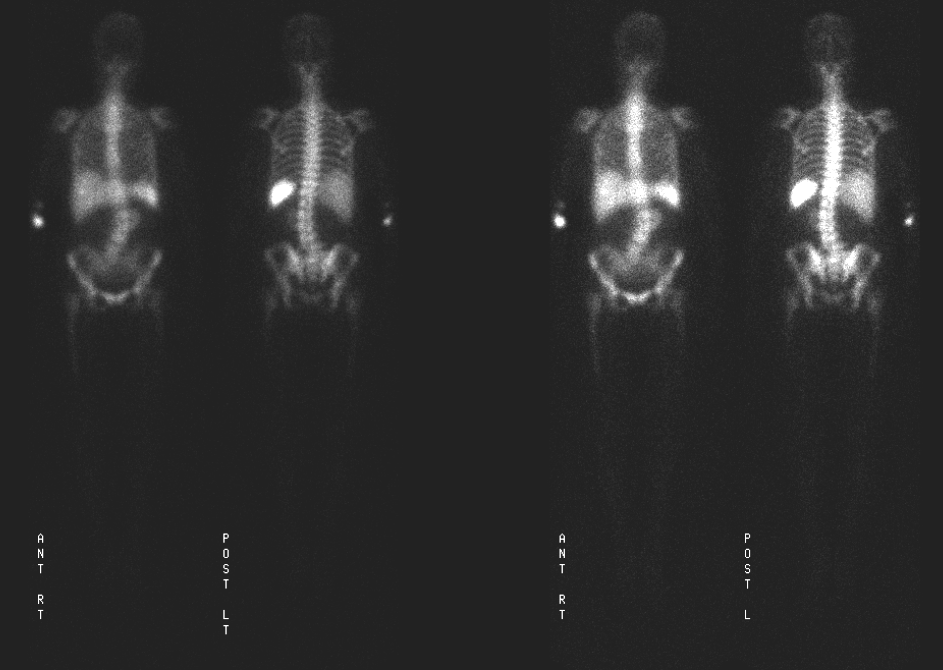

Indium Labeled WBC Scan Normal Scan Images Stock Photo Image of Labeled White Blood Cell Scan The scan works by mixing a substance called an. A radioactive scan detects abscesses or infections in the body by using a radioactive material. A labelled white cell scan is used to show areas of infection or inflammation (swelling) within the body. A radioactive scan detects abscesses or infections in the body by using a radioactive material. A 111 indium. Labeled White Blood Cell Scan.